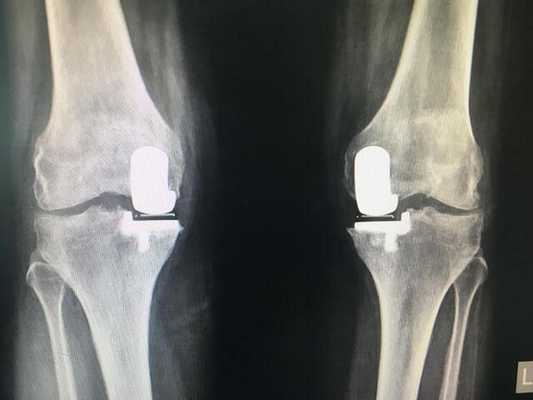

Как это выглядит после операции.

Две техники операции у одного пациента.

Одномыщелковая замена сустава на рентгене.